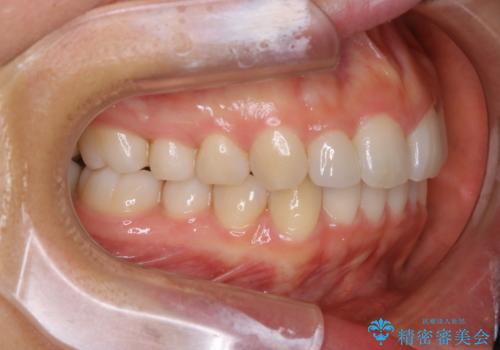

- 上の前歯が大きい事と下の前歯のがたつきを気にされてご相談にいらした方です。上の2番目の歯が矮小歯であったため、矯正治療にて歯のスペースを作った後、矮小歯には被せ物をして前歯のバランスを整えました。

歯科技工士さんとの打ち合わせを重ね、周囲の歯としっかりなじむ天然歯のような被せ物をお作りすることが出来ました。

矯正治療と補綴治療をうまく組み合わせることで、美しい口元に仕上げることが出来ました。矯正治療、補綴治療をまとめて行える総合歯科治療を体現した治療といえます。